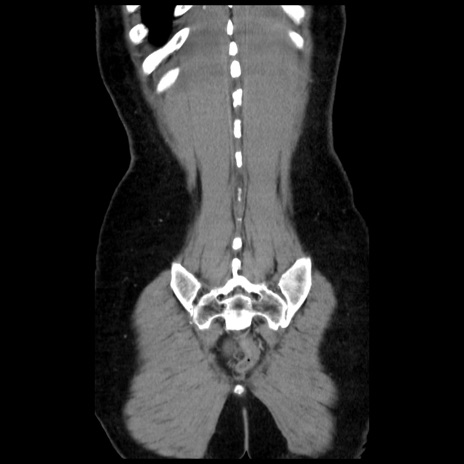

症例10(冠状断像)

【症例】 50歳代女性

【主訴】 腹痛

【現病歴】前日生レバーを食べた。今朝に排便あり。 昼前に突然発症の腹痛を生じ、当院救急外来を受診した。

【既往歴】 子宮筋腫にてで子宮全摘後

【身体所見】 意識清明、腹部:平坦、軟、下腹部やや左を中心に圧痛・反跳痛あり、筋性防御あり

【データ】WBC 7800、CRP 0.07